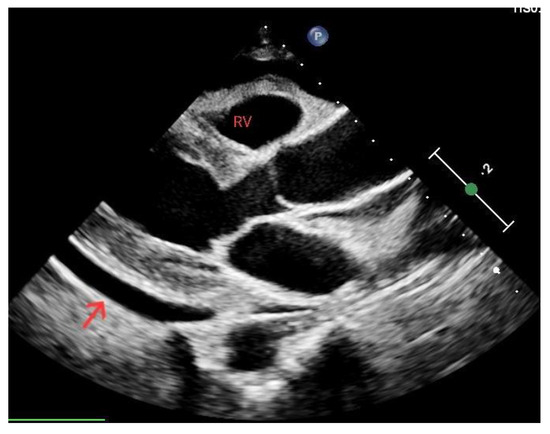

3.4.1. Cardiac Tamponade